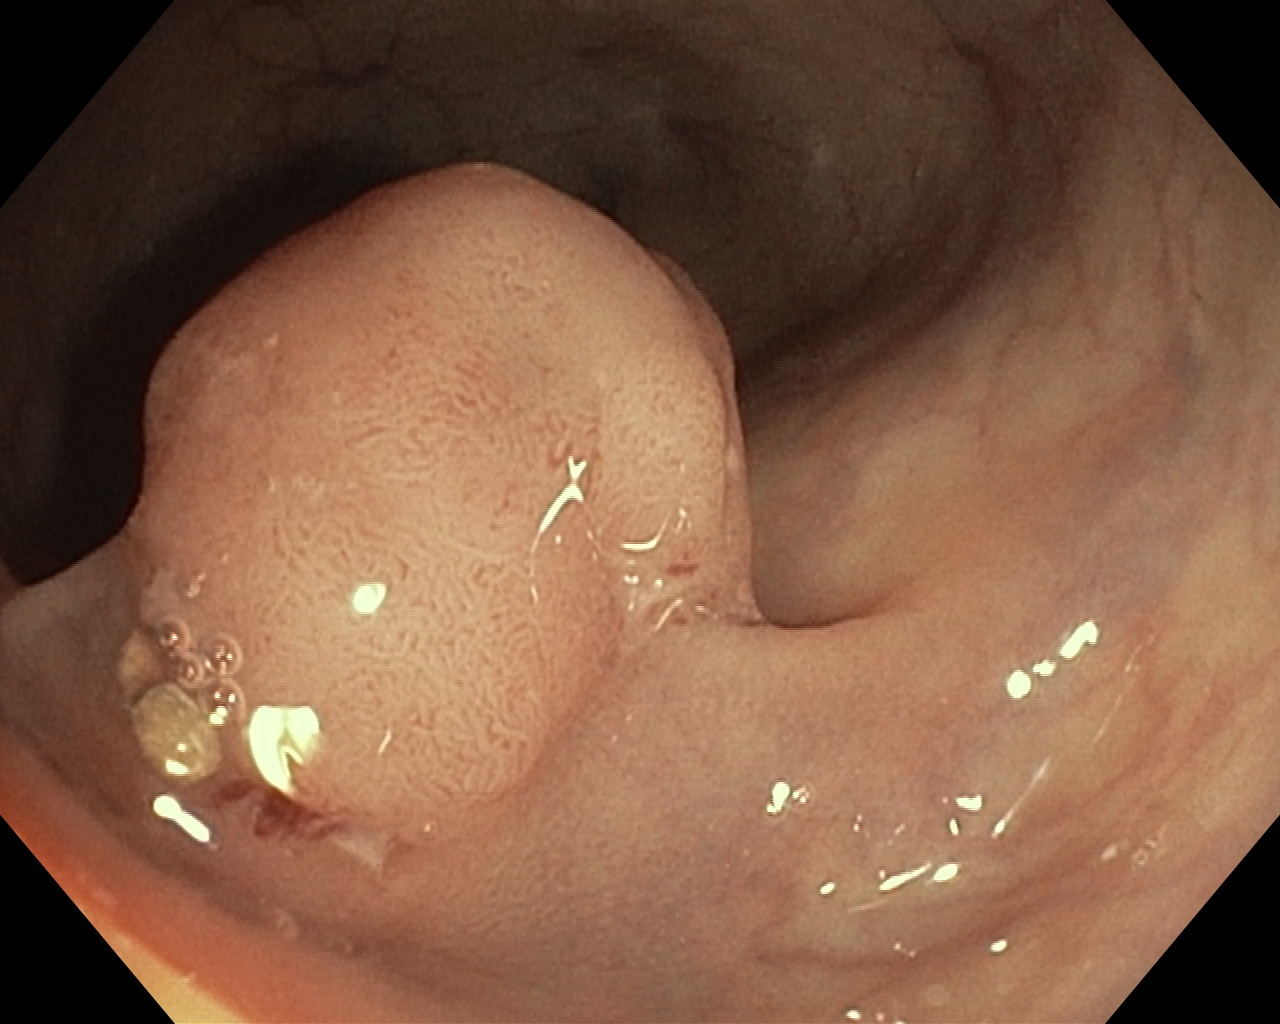

Polipy